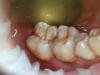

Л Ю С Я Опубликовано 23 апреля, 2013 Автор Поделиться Опубликовано 23 апреля, 2013 (изменено) Вот окончание истории: пациент сегодня пришел с жалобой на незначительный откол пломбы на жев поверхности после уик энда в воскресенье : было открытие дачного сезона и поедание шашлыков( с его то жкт!) , при прожевывание последнего куска мяса появилась незначительная болезненность при накусывании . При осмотре обнаружена про дольная трещина через всю оккл поверхность даже цепляет очень тонкой гладилкой, при этом отмечается болезненность. Думаю она изначально там и была, просто трепанация зуба и мясо помогло ее обнаружитьИнтересно на к/т изначально можно было ее увидеть? Все таки видимо есть окклюзионная травма и парафункции тоже присутствуют.Качество снимка не айс фотографировала айпадом прям с монитора, чуть позже могу перекинуть Изменено 23 апреля, 2013 пользователем Л Ю С Я Ссылка на комментарий

Whitebone Опубликовано 25 апреля, 2013 Поделиться Опубликовано 25 апреля, 2013 Вот окончание истории: пациент сегодня пришел с жалобой на незначительный откол пломбы на жев поверхности после уик энда в воскресенье : было открытие дачного сезона и поедание шашлыков( с его то жкт!) , при прожевывание последнего куска мяса появилась незначительная болезненность при накусывании . При осмотре обнаружена про дольная трещина через всю оккл поверхность даже цепляет очень тонкой гладилкой, при этом отмечается болезненность. Думаю она изначально там и была, просто трепанация зуба и мясо помогло ее обнаружитьИнтересно на к/т изначально можно было ее увидеть? Все таки видимо есть окклюзионная травма и парафункции тоже присутствуют.Качество снимка не айс фотографировала айпадом прям с монитора, чуть позже могу перекинутьПростите, я не понял. Вы лечили зуб 4.7 18-го апреля? А 23-го апреля пациент снова пришел к Вам со сколом пломбы и трещиной? А до 1-го сеанса в этом зубе была пломба, не так ли? У меня при просмотре R-снимка возникло ощущение, что пломба граничила с медиальным рогом пульпы. А при трепанации что видели? Ссылка на комментарий

Л Ю С Я Опубликовано 25 апреля, 2013 Автор Поделиться Опубликовано 25 апреля, 2013 Простите, я не понял. Вы лечили зуб 4.7 18-го апреля? А 23-го апреля пациент снова пришел к Вам со сколом пломбы и трещиной? А до 1-го сеанса в этом зубе была пломба, не так ли? У меня при просмотре R-снимка возникло ощущение, что пломба граничила с медиальным рогом пульпы. А при трепанации что видели?Не было изначально никакой пломбы и кариеса вообще! А скол произошел вр пломбы ( сиц) не характерный для временной ровно посередине окк поверхности. Ссылка на комментарий